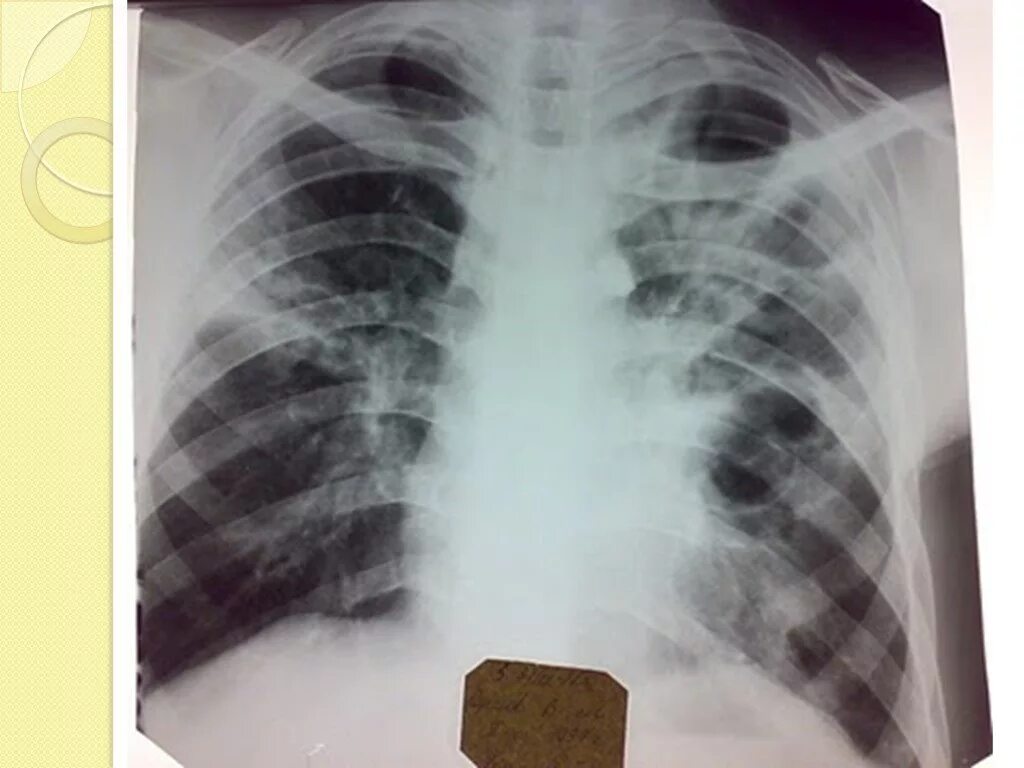

Как выглядит фиброз легких